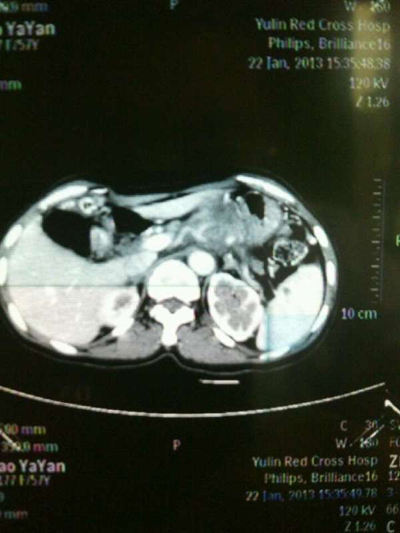

我院肝胆外科主治医师张洪昌医生介绍,赵大妈患上的是中晚期胰体尾肿瘤,瘤体很大,毗邻腹腔、肝脏、肠系膜、肾等多个器官重要血管,手术难度较大,风险极高。由于胰腺和胃的关系密切,所以引发了强烈的胃痛。

术前CT检查